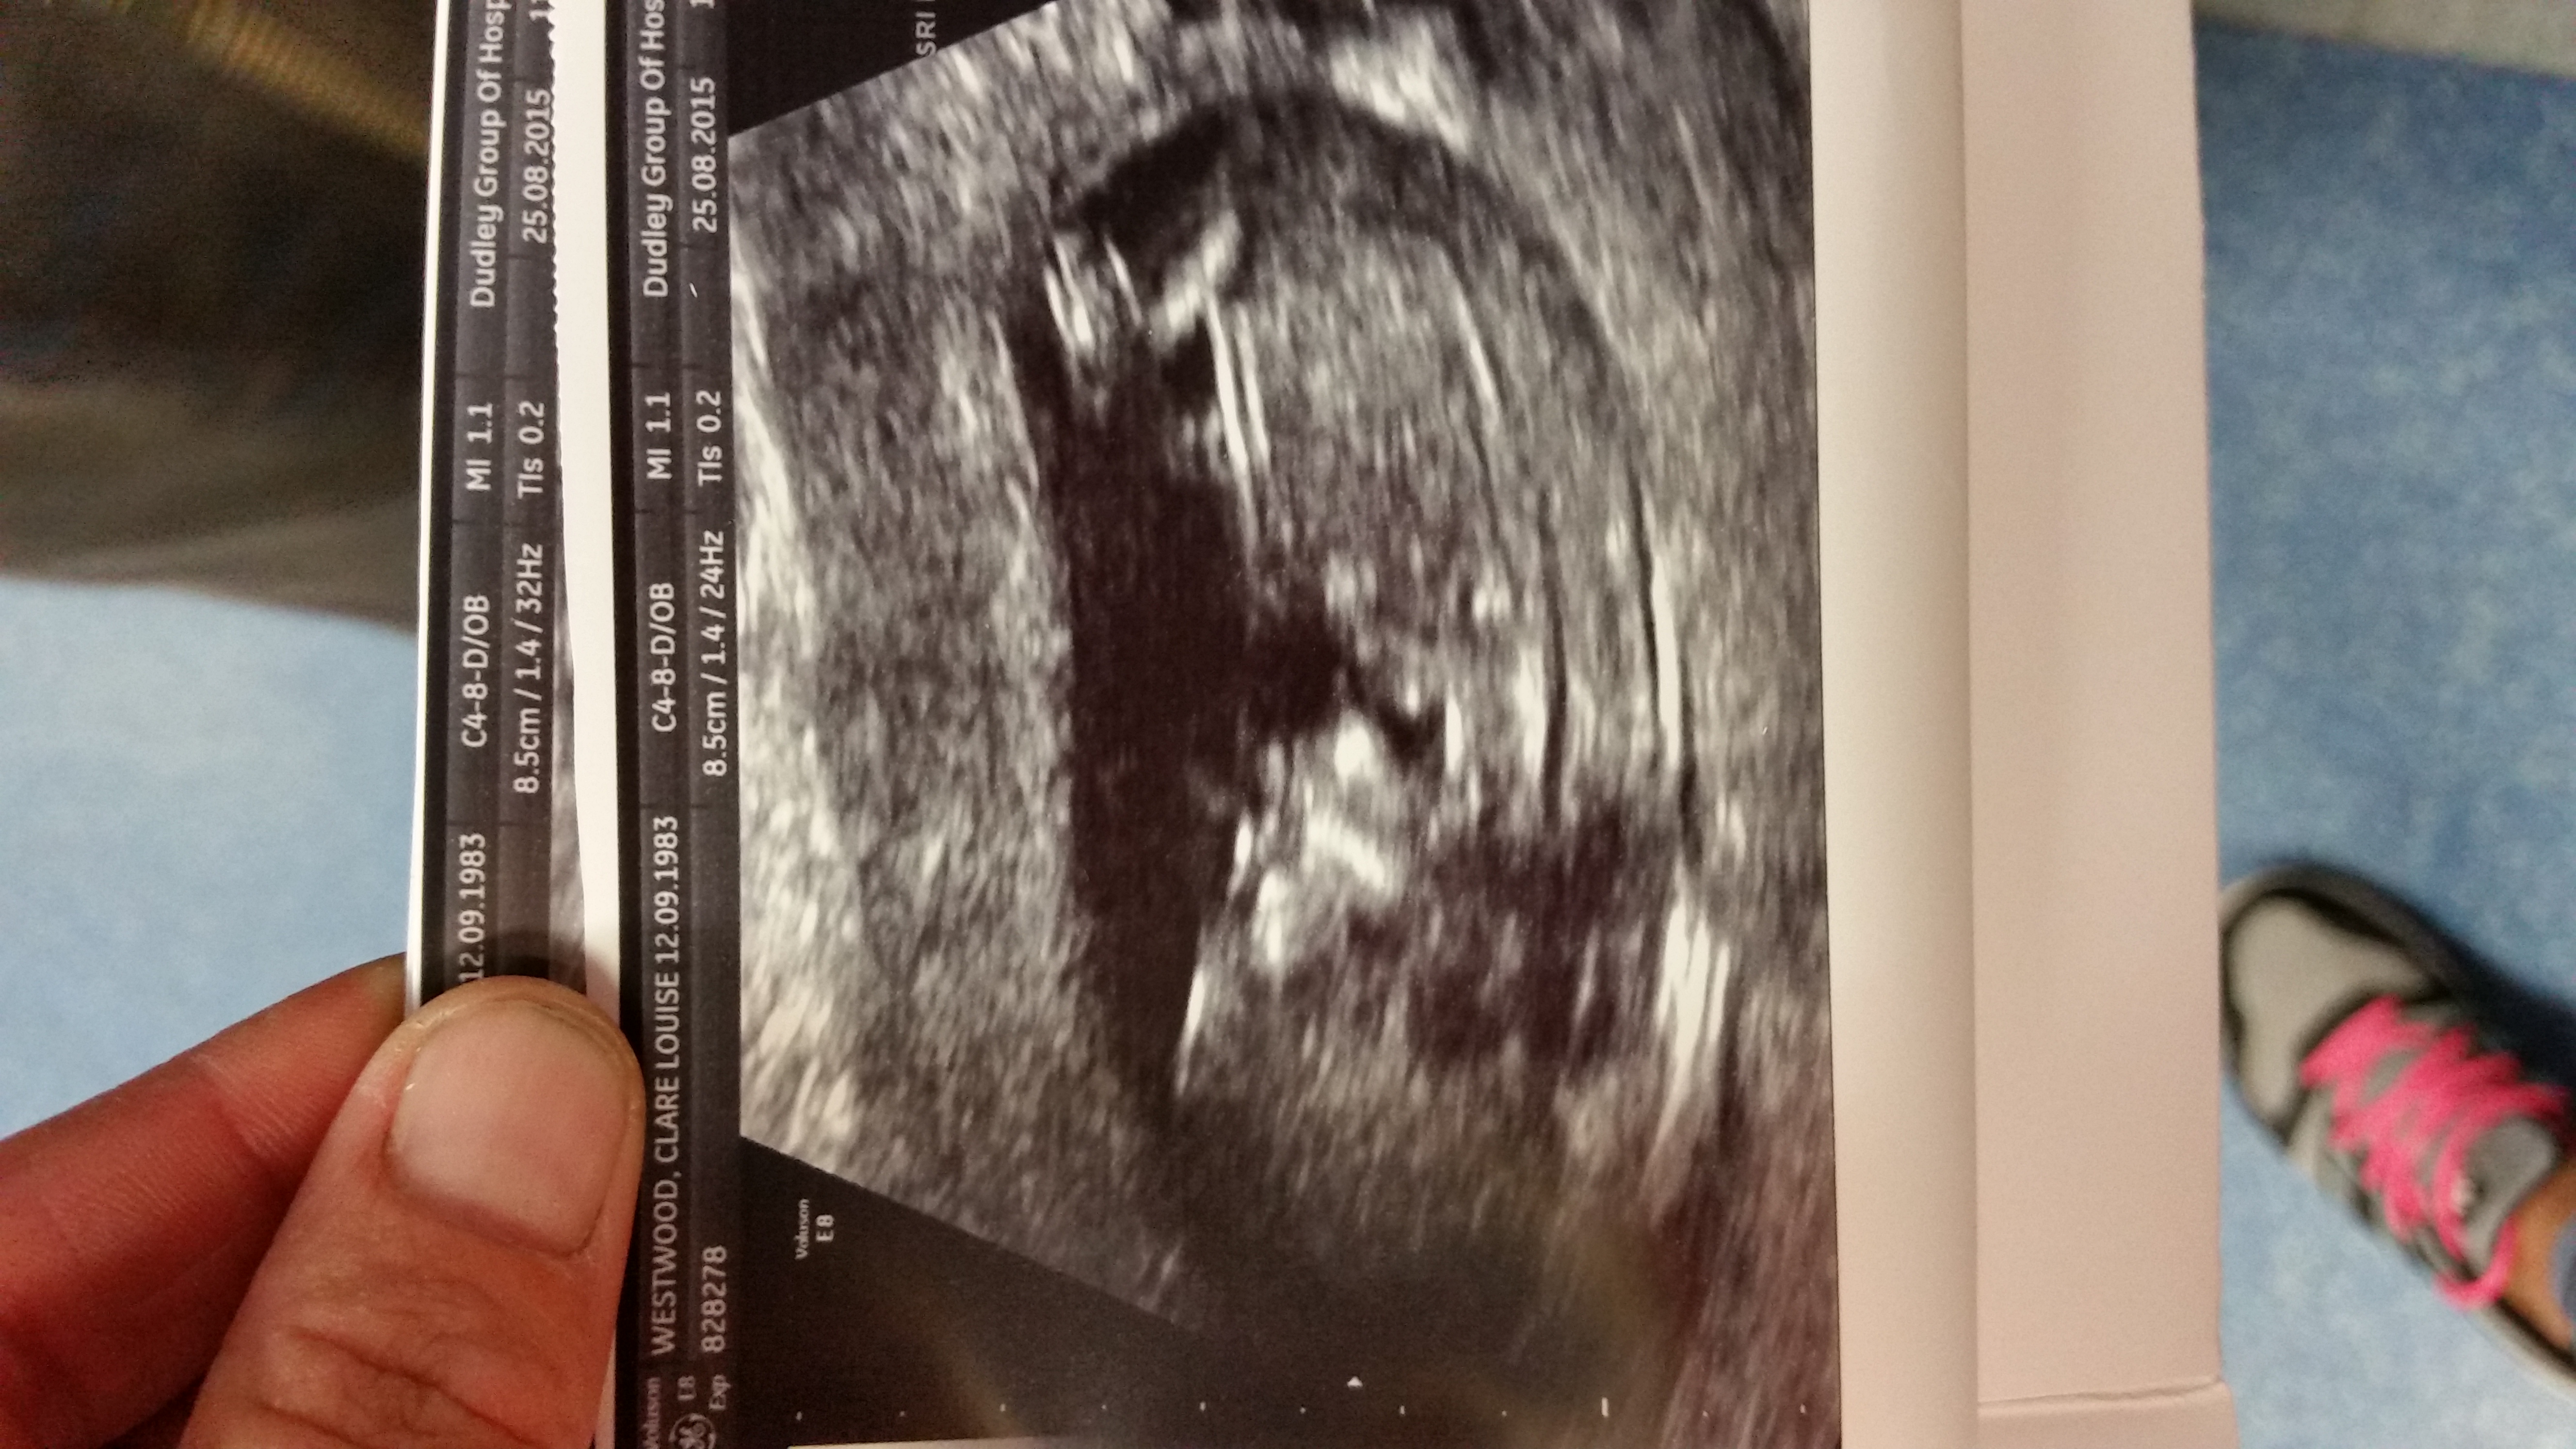

Please can some one guess the gender using skull theory I can't make nub out thank you xx

If that's the nub I think I'm seeing, possibly girl.

Hi Clare. I can't see a nub and I pay no heed to skull theory. It was wrong on all 3 of my sons. I know the wait is horrid. Good luck xoxo

No gender clues for me